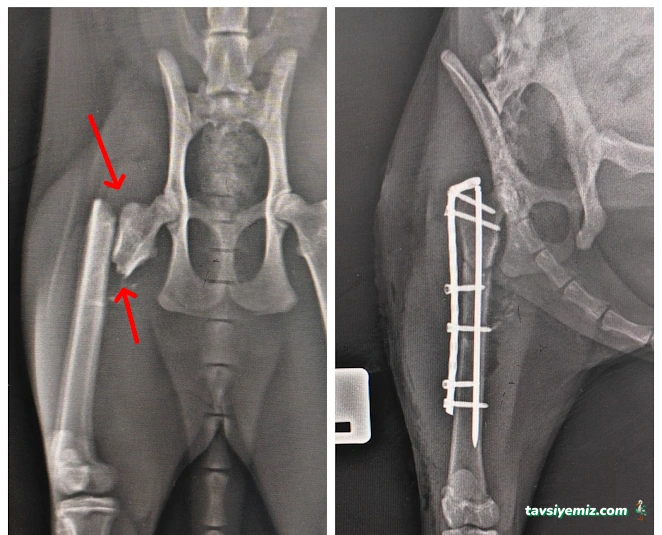

Ameliyatlar Kısırlaştırma, tümör alımı, yumuşak doku operasyonları